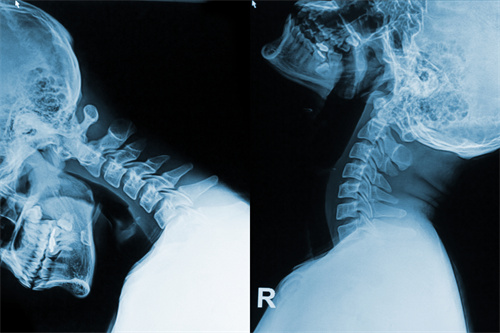

忙碌了一年,我们的颈椎真的还健康吗?